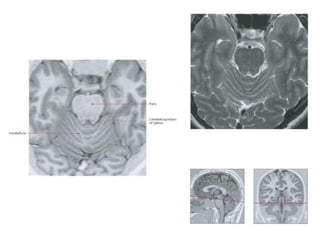

• The tegmentum (from Latin for "covering”) is

• The midbrain tegmentum is the part of the

midbrain extending from the substantia nigra

to the cerebral aqueduct in a horizontal

section

• The tegmentum(from Latin for "covering”) is a general area within the brainstem. It is located between the ventricular system and distinctive basal or ventral structures at each level. • The midbrain tegmentum is the part of the midbrain extending from the substantia nigra to the cerebral aqueduct in a horizontal section • The nuclei of CN III and IV are located in the tegmentum portion of the midbrain.